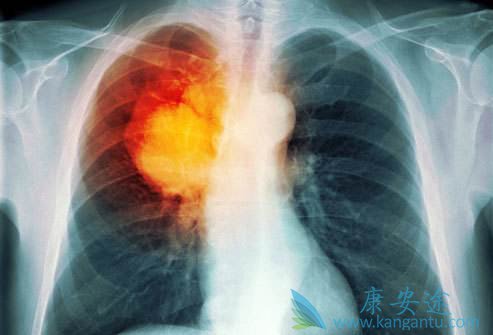

肺癌发展到了肺癌晚期有什么症状

肺癌晚期有什么症状

发生区域性扩散的肺癌晚期患者几乎都有不同程度的气促。由肺和心肌产生的正常组织液由胸正中的淋巴结回液。若这些淋巴结被肿瘤阻塞,这些组织液将积聚在心包内形成心包积液或积聚在胸腔内形成胸腔积液。以上两种情况均可导致气促。控制左侧发音功能的喉返神经由颈部下行至胸部,绕过心脏的大血管返行向上至喉,从而支配发音器官的左侧。因此,若肿瘤侵及纵隔左侧,使喉返神经受到压迫,声嘶便产生了,但却无咽痛及上呼吸道感染的其它症状。

出现疼痛往往提示癌症已进入中、晚期。开始多为隐痛或钝痛,夜间明显。以后逐渐加重,变得难以忍受,昼夜不停,剧烈疼痛是肺癌晚期临终前症状,若是出现一般通过药物进行控制。疼痛一般是癌细胞侵犯神经造成的。很多人晚期都会感到无比疼痛,甚至吃药都不管用。由于某些体表癌的癌组织生长快,营养供应不足,出现组织坏死所形成的。如某些乳腺癌可在乳房处出现火山口样或菜花样溃疡,分泌血性分泌物,并发感染时可有恶臭味。此外,胃、结肠癌也可形成溃疡,一般只有通过胃镜、结肠镜才可观察到。